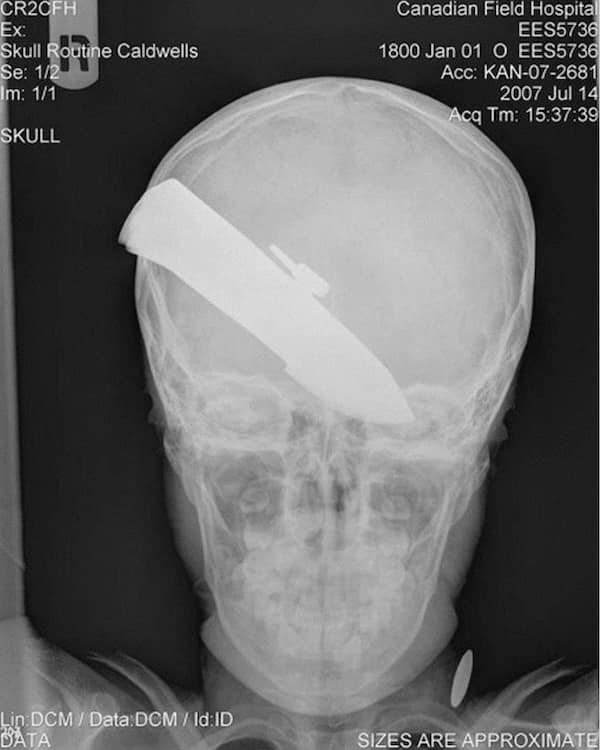

Weird xray photos

I used to think that nothing could surprise me anymore—until I stumbled upon some weird x-ray photos that made me reconsider my stance on human ingenuity (or lack thereof). Apparently, some people have a knack for getting objects lodged where they absolutely shouldn’t be. If you’ve ever wondered how not to use everyday items, these images might provide some unintended guidance.

This collection showcases 31 bizarre x-ray images that defy logic and anatomy textbooks alike. Each photo reveals unexpected objects making cameo appearances inside the human body, turning medical imaging into a gallery of the absurd. From common household items inexplicably found in unusual places to anomalies that would leave even seasoned doctors scratching their heads, these images offer a perplexing glimpse into the more “creative” side of medical emergencies. They highlight the intersection of curiosity, misadventure, and perhaps a dash of poor decision-making, all captured through the lens of radiology.